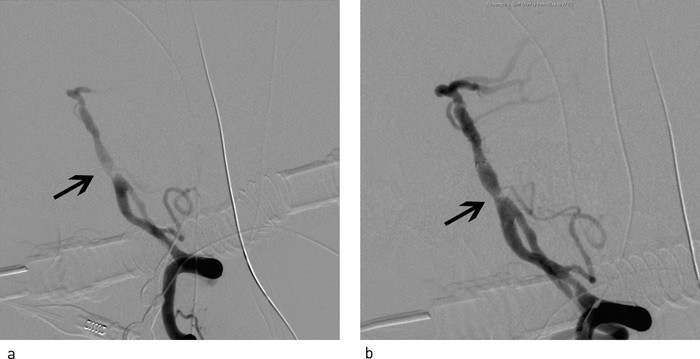

Ved cerebral angiografi fant man at det forelå en 90 % distal venstresidig stenose i a. carotis interna med redusert blodgjennomstrømming av venstre hjernehalvdel (fig 1a). Angiografisk bedømt forelå det få kollateraler og forsinket blodgjennomstrømming i venstre cerebrale hemisfære via a. comunicans anterior og a. comunicans posterior. Det var indikasjon for angioplastikk av stenosen. Ved bruk av ballongkateter (Maverick II) ble stenosen dilatert. Angiografisk ble reststenosen beregnet til 46 % (fig 1b). Etter ett døgn i intensivavdeling og to dager i slagavdeling ble pasienten utskrevet til hjemmet med uendret platehemmende medikasjon. Han var da symptomfri og uten svakhet i høyre hånd. Ved poliklinisk kontroll fire måneder senere var han fortsatt symptomfri, og blodtrykket var spontant normalisert.